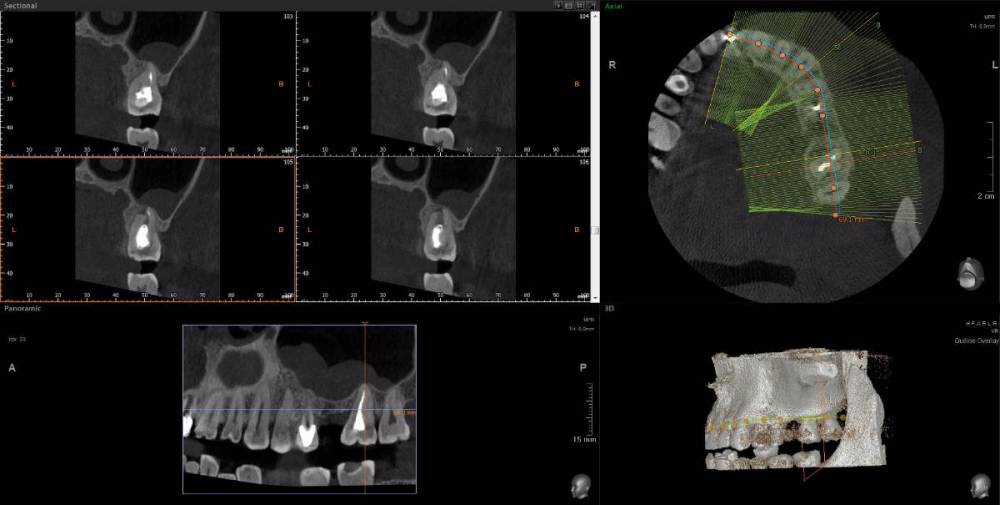

wladdX Опубликовано 15 апреля, 2021 Поделиться Опубликовано 15 апреля, 2021 Несколько скриншотов из вашей КЛКТ. Зуб 25: Зуб 27: Правая сторона: 1 Ссылка на комментарий

red_butler Опубликовано 16 апреля, 2021 Поделиться Опубликовано 16 апреля, 2021 1.5 1.6 перелечивать, 2.4 похоже кариес корня, нужно смотреть очно, 2.5 парадонтологическое поражение, смотреть очно, 2.6 ревизия корневых каналов Ссылка на комментарий